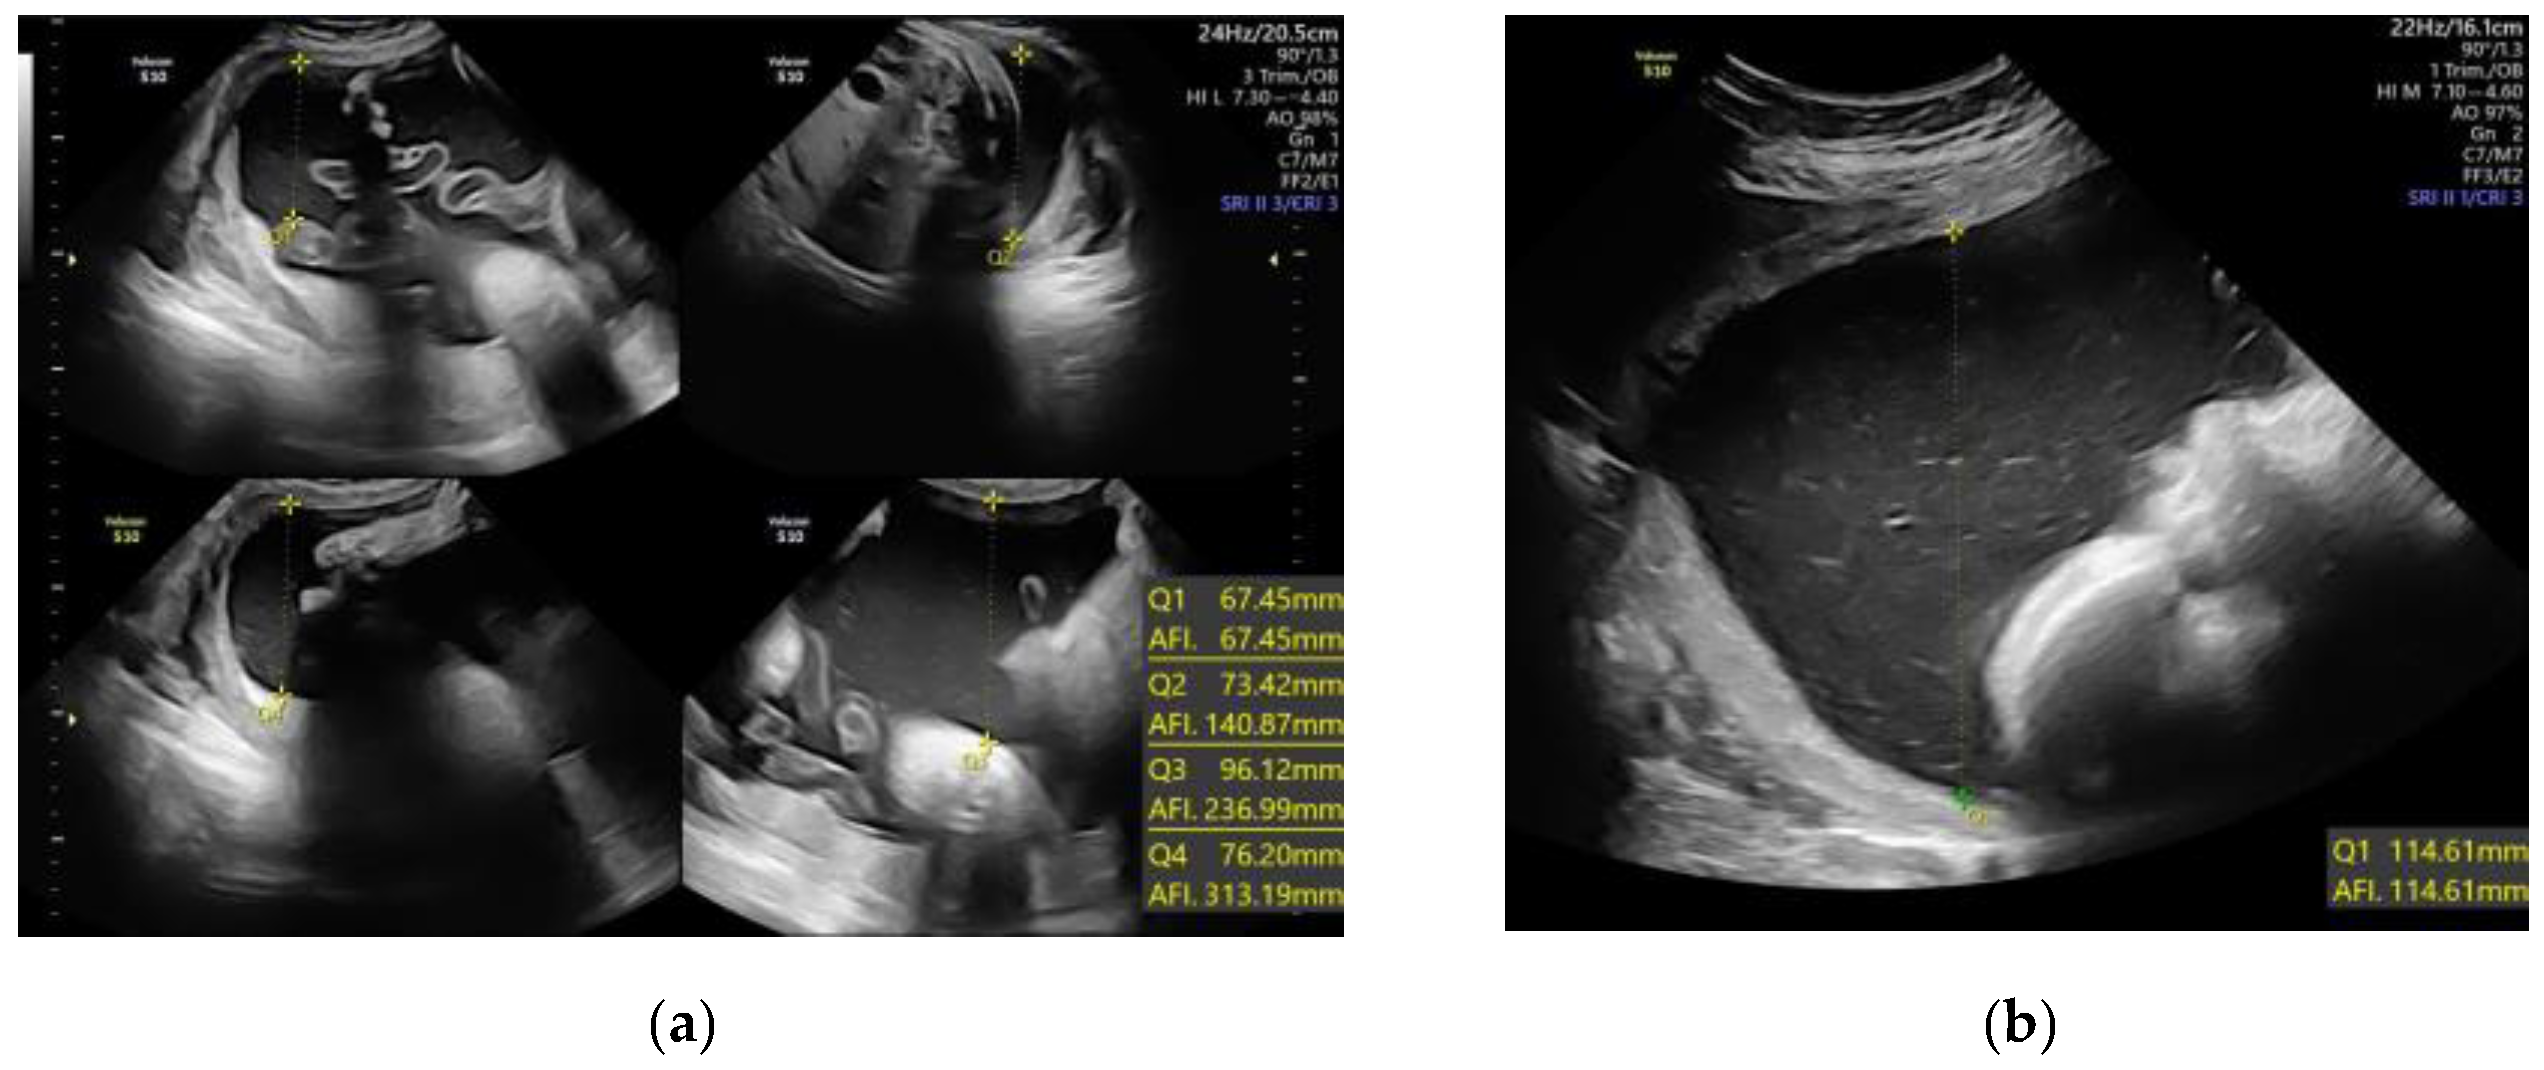

2. Materials and Methods

3.2. AFV and Their Association with Adverse Maternal and Perinatal Outcomes